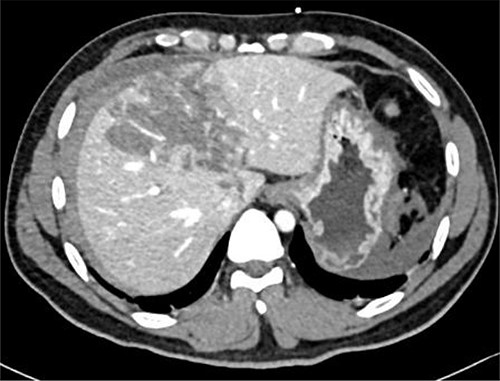

Repeated CT scan on Day 5 showing liver laceration with no evidence of hepatic pseudoaneurysm.

Resuscitation was carried on with 2 l of normal saline and two PRBC units to stabilize the patient. The computed tomography (CT) scan identified Grade 4 liver injury with hemoperitoneum (Fig. 2). Subsequently, the multiple bone fractures underwent surgical fixation, and post-operatively, he was hemodynamically stable. On the fifth day after admission, repeated CT scan demonstrated the liver injury with no evidence of hepatic pseudoaneurysm (Fig. 3). The patient remained stable with tolerated feeding with no abdominal pain or distension. On the Day 17, he developed abdominal pain mainly in the epigastrium, which was associated with nausea and deep epigastric tenderness. Abdominal ultrasound (US) (Fig. 4) and CT scan (Fig. 5) revealed complex, large intraparenchymal hepatic pseudoaneurysm (measuring about 58 × 41 × 30 mm) related to the left hepatic artery Segment 4 branch with surrounding hematoma located mainly at segment 4B/A ,and there was another tiny pseudoaneurysm seen at Segment 4A. Selective angiography confirmed the diagnosis of pseudoaneurysm with multiple blood supplies from Segment IV and Segment II.